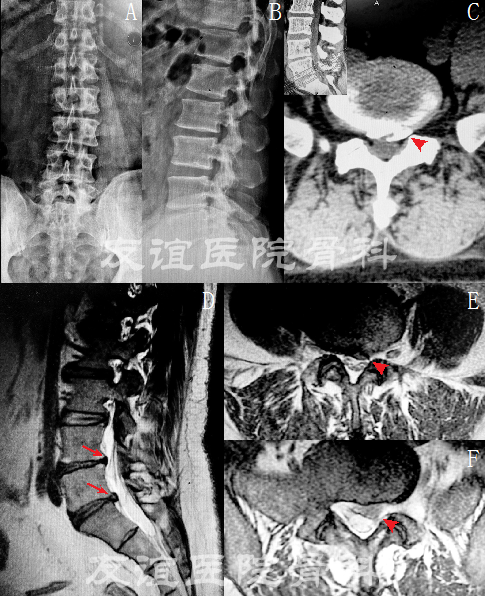

图1:术前影像学资料:腰椎正侧位片(A,B)提示:L4-5,L5-S1椎间隙明显变窄

术前CT(C)提示:L5-S1左侧椎间盘突出伴骨化

术前MRI(D-F)提示:L5-S1(F)左侧腰椎间盘突出压迫硬膜囊及左侧神经根,L4-5(E)左侧椎间盘突出。(红色箭头标记腰椎间盘突出)